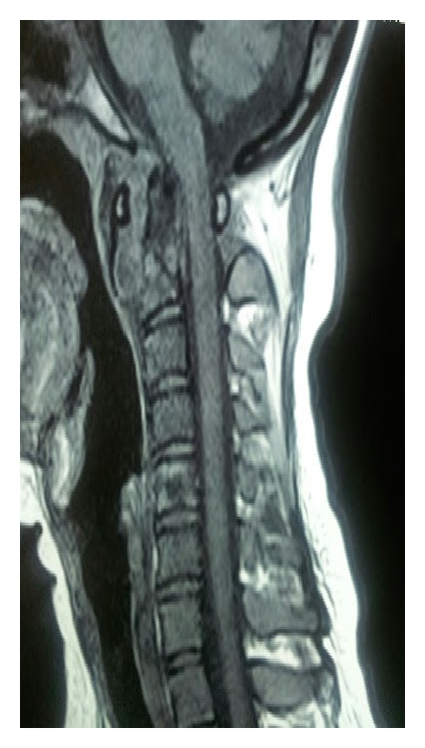

A 24-year-old unmarried female presented to the outpatient clinic with painful swelling of the right sternoclavicular joint of 2-month duration without any discharging sinus (Figure 1). The swelling was gradually increasing in size and was accompanied with mild pain. The pain was dull, continuous, and limited to the site of the lesion. She also complained of neck stiffness and pain on neck movements. There was no history of any injury. History of cough, weight loss, night cries (severe pain at night), and low grade fever was present for the past 4 months. There was no history of previous tuberculosis or contact with an open case of tuberculosis. She had been prescribed several antibiotics and analgesics at another centre but had no symptomatic improvement. On physical examination the swelling (cm) was present over right sternoclavicular joint and was associated with presence of mild tenderness, erythema, and local rise of temperature. Laboratory tests revealed haemoglobin of 10.4 gm%; total leukocyte count was 10.300/mm3. Her ESR was 34 mm in first hour. She was negative for HIV based on ELISA method. On radiographic evaluation there was destruction with sclerosis on the medial end of the right clavicle along with features of diffuse pulmonary infiltrate (Figure 2). MRI revealed bilateral upper lung lobe infiltrate with arthritis of right sternoclavicular joint, with regional fluid collection. A destruction of the atlanto-axial junction, D7-8 intervertebral disc space along with a pus collection from D5 to D8 region could also be appreciated (Figures 3(a), 3(b), and 3(c)). An early morning sputum sample was sent for Ziehl-Neelsen (ZN) staining and it came out positive suggesting the diagnosis of pulmonary tuberculosis. Fine needle aspiration of the right sternoclavicular lesion was done using a 22-gauge needle and sent for Gram staining, staining for acid-fast bacilli (AFB), histopathology, and cultures including a tubercular culture. The histologic picture was that of chronic inflammation with a caseating granuloma compatible with tuberculosis. The Ziehl-Neelsen stained smear also showed the presence of acid-fast bacilli (AFB), confirming the diagnosis of tuberculosis. The culture for Mycobacterium tuberculosis came out as negative. Antitubercular chemotherapy with four first line antitubercular drugs (rifampicin, isoniazid, ethambutol, and pyrazinamide) was started. The patient had a good clinical response within 6 weeks and was switched to three drugs (rifampicin, isoniazid, and ethambutol) after 3 months of therapy with four drugs. The clinical, haematological, and radiological parameters showed complete healing of the lesion after 1 year of treatment with ATT, which was further continued for a total duration of 18 months. After successfully completing the therapy for 18 months, the patient was followed up for 2 years and showed no recurrence of symptoms.

(a)

(b)

(c)